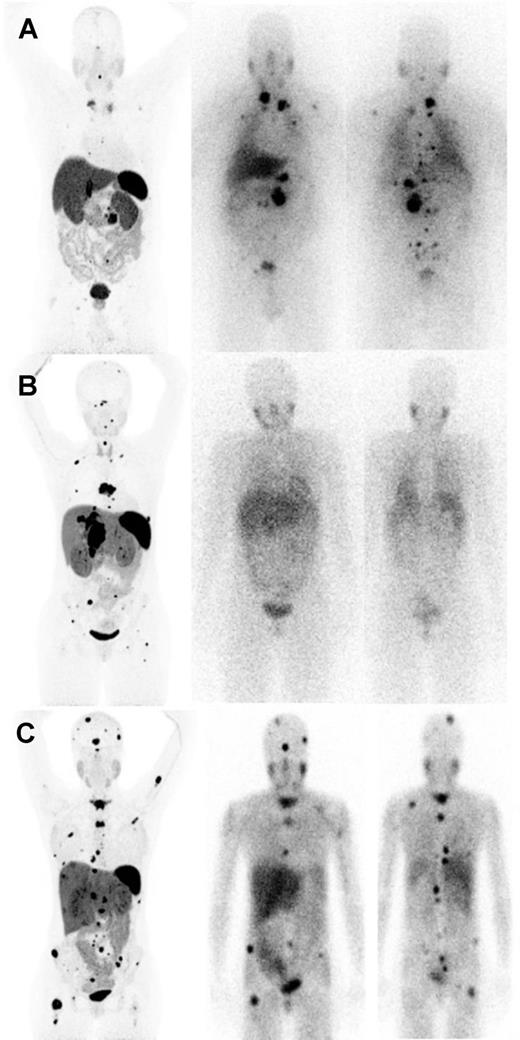

The choice between 131 I-MIBG and 177 Lu-DOTATATE in many cases becomes obvious when lack of uptake is observed with one radiopharmaceutical and not the other, as is frequently seen (Fig. 2A and B). The most important conundrum occurs when both 123 I-MIBG and SSTRI scans demonstrate similar uptake and extent of disease (Fig. 2C).

Selection of HSA- 131 I-MIBG versus PRRT for metastatic pheochromocytoma/paraganglioma based on expression of somatostatin receptor and norepinephrine transporter. A, Superior detection of tumors by norepinephrine transporter imaging by 123 I-MIBG (anterior and posterior planar images on the right) compared with SSTRI by 68 Ga-DOTATATE PET/CT [maximum intensity projection (MIP) image on the left] in a 64-year-old man revealing a recurrent tumor in the left adrenalectomy bed along with retroperitoneal lesions, left supraclavicular lymph node, and multiple scattered bony metastatic disease, including cervical bone metastasis. B, Superior detection of tumors by 68 Ga-DOTATATE PET/CT (MIP image on the left) compared with 123 I-MIBG (anterior and posterior planar images on the right) in a 33-year-old woman revealing an extensive recurrent tumor in the right adrenalectomy bed at the level of right mid kidney along with metastatic disease in both lungs, scattered bone metastases in vertebral bodies, axial, and proximal appendicular skeleton. The planar images of 123 I-MIBG only reveal mild uptake of recurrent tumor in the right adrenalectomy bed. C, Similar pattern of tumor detection by both 68 Ga-DOTATATE PET/CT (MIP image on the left) and 123 I-MIBG (anterior and posterior planar images on the right) in a 27-year-old female patient revealing metastatic liver lesions and multiple scattered bony metastatic disease. While interpreting the scans, it is critical to account for the inherent differences between single-photon emission imaging ( 123 I-MIBG scintigraphy) and PET ( 68 Ga-DOTATATE) imaging as contrast recovery, sensitivity, and spatial resolution are far superior for PET imaging. Therefore, some of the smaller lesions seen on 68 Ga-DOTATATE MIP may not be visible on planar images of 123 I-MIBG scintigraphy, despite adequate MIBG uptake. This should not be confused for greater uptake or a higher likelihood of response to therapy. 124 I-MIBG 18 F-FDA and 18 F-MFBG for PET that are under development should help simplify the comparison between MIBG and SSTRI scans in a given patient.